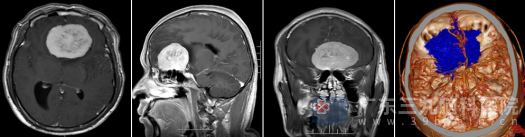

入院后,医院为苏某安排了详细的术前头颅MR检查。影像结果显示:前颅窝底示一团块状占位性病变,大小约为57.0×52.0×44.0mm(相当于一个较大鸡蛋大小),且增强后呈现明显异常强化影。这个位置毗邻重要的神经和血管,手术难度极大。

术前MR